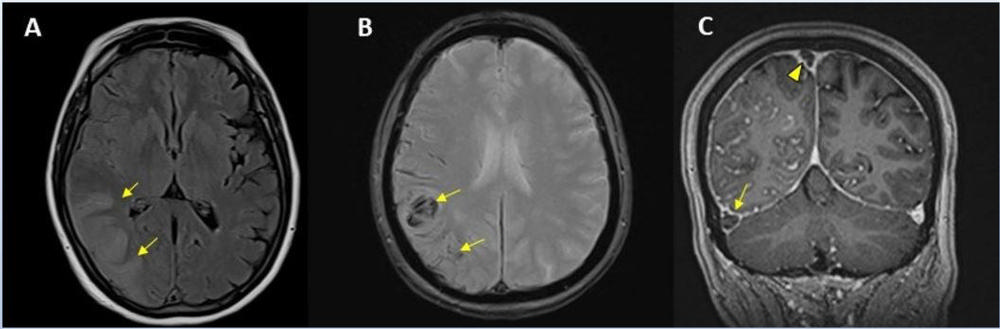

Figure 7. Hemorrhage seen in 56-year-old female with COVID-19 infection and no other significant past medical history.

Figure 8. 65-year-old male smoker, presented with acute hypoxic respiratory failure secondary to COVID-19 pneumonia, requiring intubation. Hospitalization was complicated by seizures relating to cerebral edema and hemorrhagic posterior reversible encephalopathy syndrome.